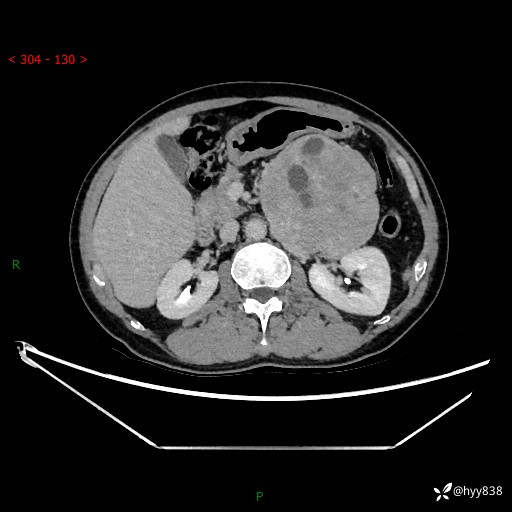

年龄:61岁

主诉:发现腹膜后肿瘤3天

腹部CT平扫+增强(动脉期+静脉期)